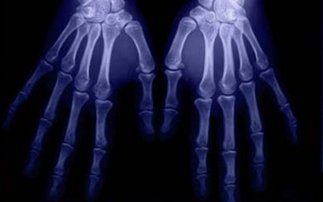

με οστό, το μπορεί να αξιοποιηθεί από τους ορθοπεδικούς για την αντιμετώπιση καταγμάτων, από τους οδοντίατρους, αλλά και άλλους γιατρούς.

Το εκτυπωμένο καινοτομικό υλικό συνδυάζεται με φυσιολογικό οστό, φτιάχνοντας μια «σκαλωσιά», πάνω στην οποία μπορεί ύστερα να αναγεννηθεί πλήρως ένα κατεστραμμένο οστό. Στη συνέχεια, το εκτυπωμένο υλικό βιοδιασπάται στον οργανισμό, χωρίς να προκαλεί παρενέργειες.

Οι ερευνητές, με επικεφαλής την καθηγήτρια Σουσμίτα Μπόζε της Σχολής Μηχανολόγων και Νέων Υλικών έχουν ήδη κάνει επιτυχημένες εργαστηριακές δοκιμές με πειραματόζωα, όπως ποντικούς και λαγούς.

Θεωρείται πιθανό ότι το νέο οστικό υλικό, το οποίο θα διαμορφώνεται κατά παραγγελία και ανάλογα με τις ανάγκες του κάθε ασθενούς, θα είναι διαθέσιμο σε λίγα χρόνια και για τους ανθρώπους.

Σύμφωνα με την επικεφαλής αφού ο αρμόδιος γιατρός κάνει μία τομογραφία της οστικής βλάβης, η τομογραφία θα μετατρέπεται σε αρχείο CAD (σχεδιασμός με τη βοήθεια υπολογιστή) και θα στέλνεται στον εκτυπωτή.

Ο εκτυπωτής ψεκάζει το νέο υλικό σε διαδοχικά στρώματα πάχους 20 εκατομμυριοστών του μέτρου, δηλαδή περίπου με το μισό πλάτος μιας ανθρώπινης τρίχας. Μετά από μία εβδομάδα, το νέο υλικό, σε συνδυασμό με ανθρώπινα κύτταρα οστού, μπορεί πλέον να υποστηρίξει τη δημιουργία νέων υγιών οστικών κυττάρων.